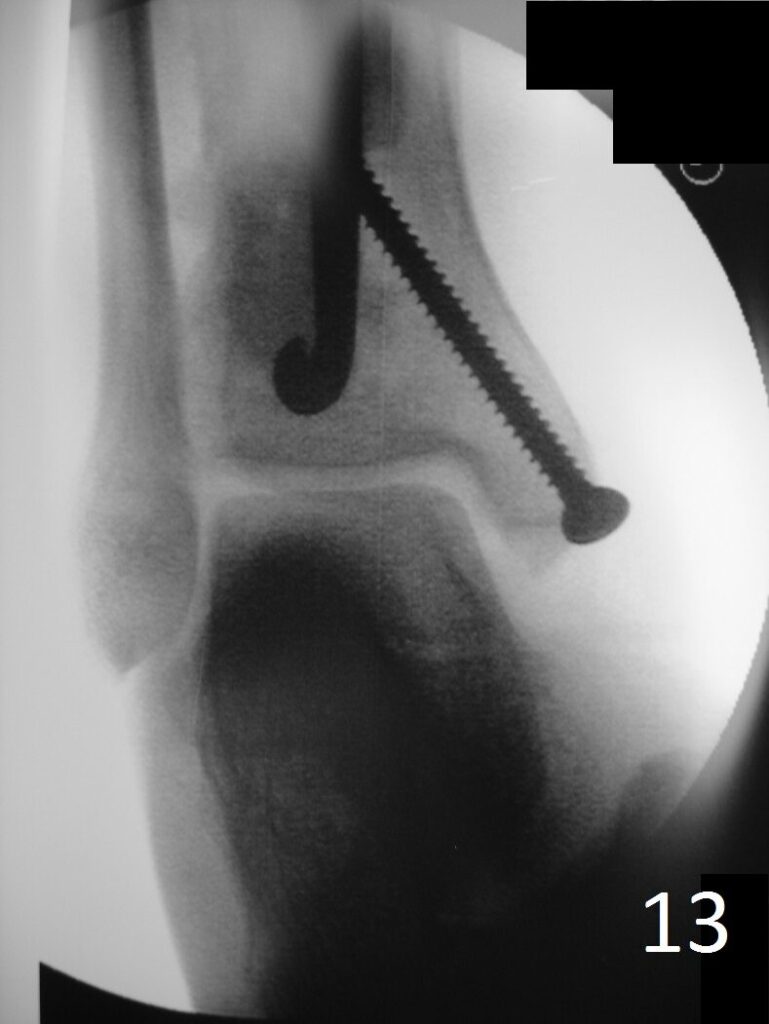

Fig. 6-12: Intraoperative photograph of the lesion (Fig. 6) and steps of the treatment (Fig. 7-12), excision, cryosurgery, gross specimen and cemented internal fixation

Fig. 13: Postoperative image of distal tibia-fibula shows the fixation.